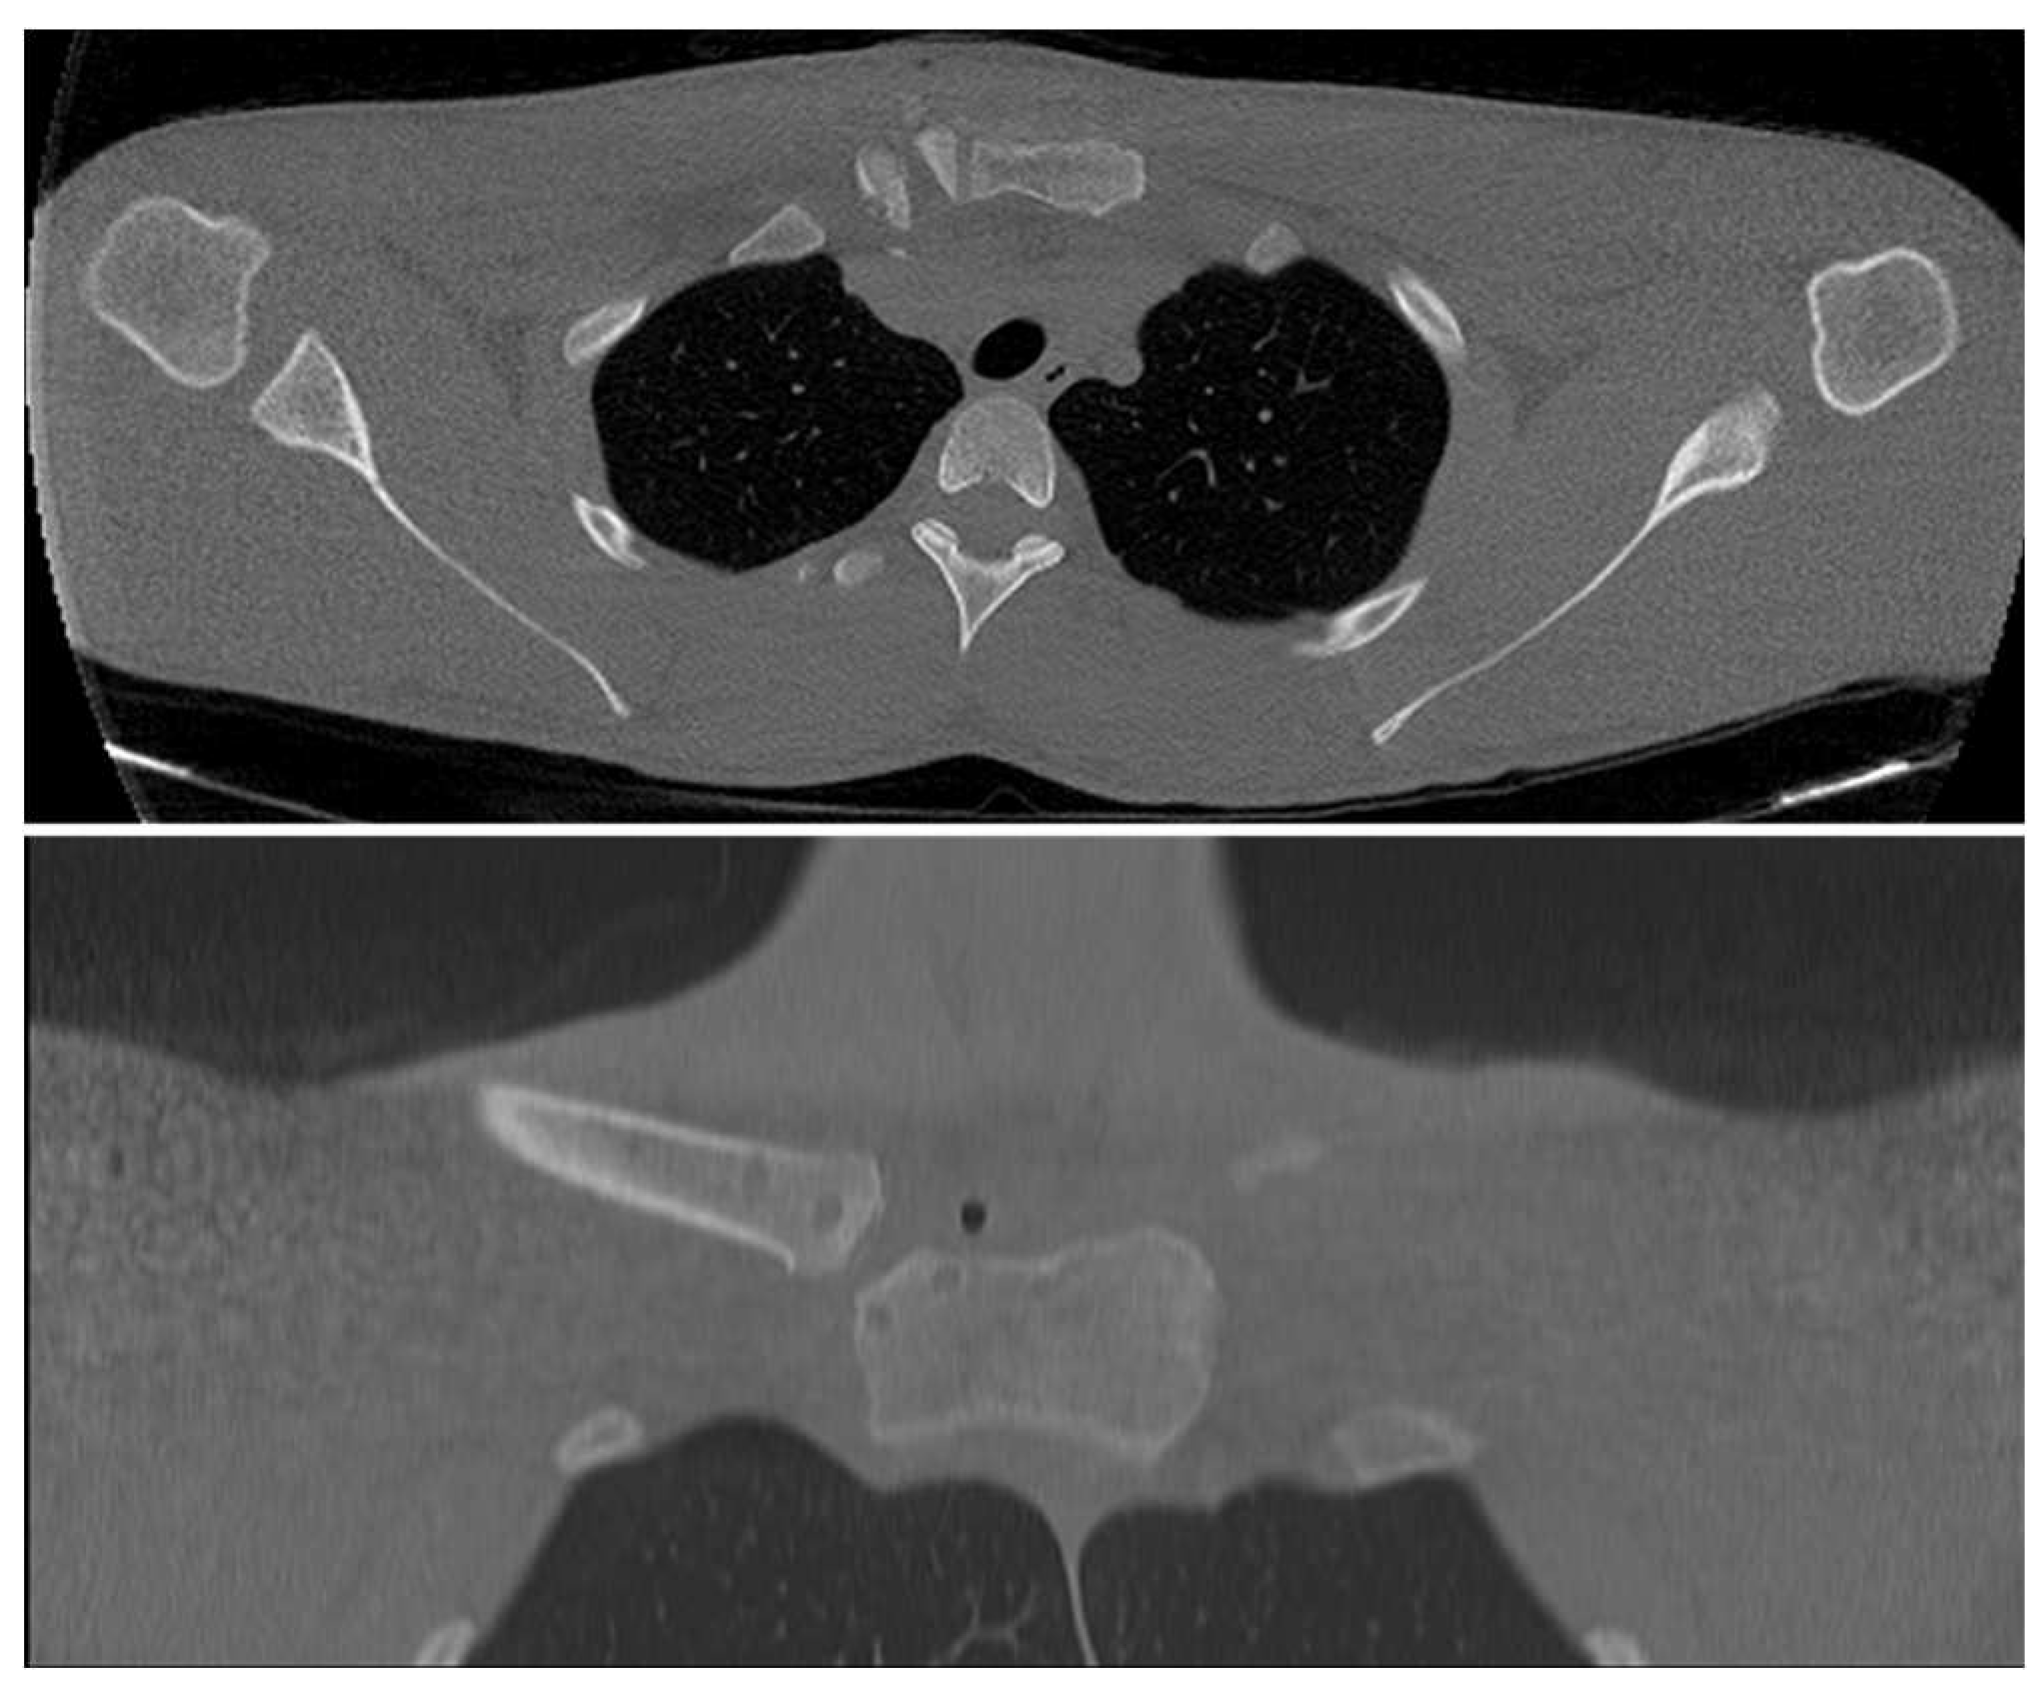

Second stage was an open reduction of the SCJ and subsequent stabilization with the autologous semitendinosus tendon graft (Figure 3). In the same supine position and in a sterile field, we proceeded to exposing the SCJ, the sternal manubrium and the medial clavicle through an antero-superior straight incision extended from the middle part of the clavicle to the mid superior aspect of sternal manubrium, finding a posterior dislocation of the SCJ. After releasing the medial part of the clavicle and the articular facet of the sternum, four bone tunnels (diameter 5 mm) were arranged, two in the clavicle and two in the sternum, adequately protecting the noble structures underlying. After the reduction of the clavicle, we stabilized the joint with a figure-of-eight semitendinosus tendon graft reconstruction and then reinforced it with high strength suture tape (Figure 4). A suction drainage was also positioned after appropriate hemostasis and wash. As per post operative protocol an arm sling was recommended. Elbow, wrist and hand mobilization were allowed from day 1; at 3 weeks the patient started the rehabilitation of the shoulder. At 2 months, a new CT scan was performed and it showed a complete reduction, both on the axial and the coronal view (Figure 5 and Figure 6).

Figure 5. Postoperative CT scan, 1st patient: reduction confirmed on axial and coronal scan.

Figure 6. Pre and postoperative CT scan, 2nd patient: reduction confirmed on axial and coronal scan.